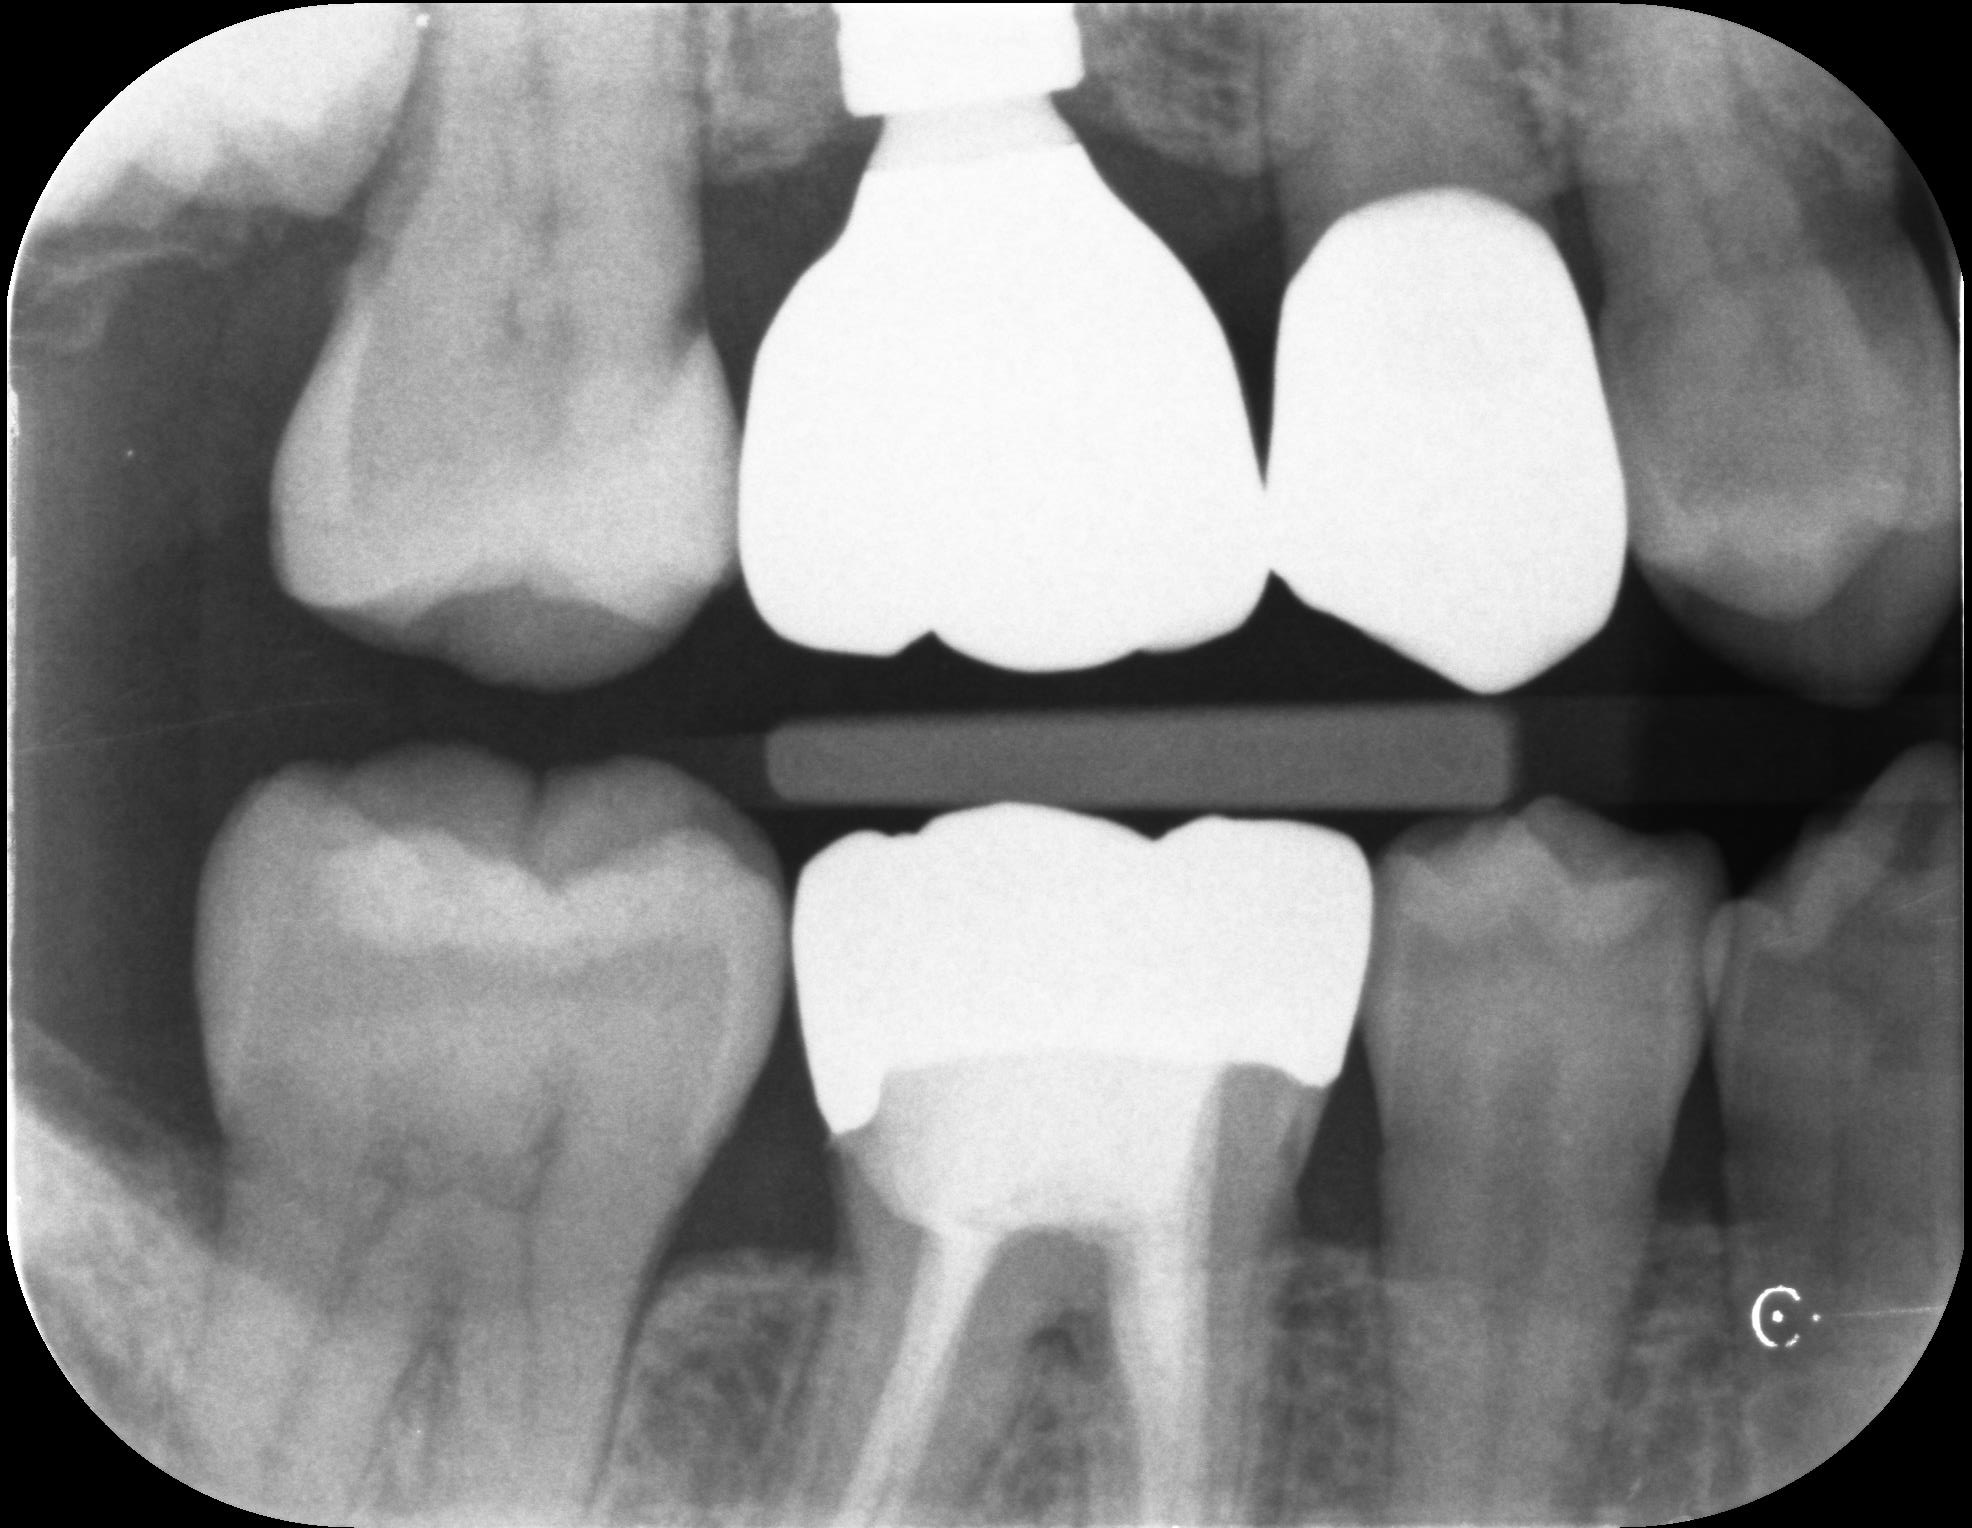

下記の写真は初診時から1年毎に撮影したレントゲンです。

写真の赤丸部分を見ていただくとわかるように、レントゲンで白く見えていた部分が黒くなってきていることがわかります。虫歯が大きくなってくると、このような変化がレントゲンで確認できるようになります。こういった変化を早期に捉え、最小限の治療介入で終わらせることが歯の長期予後につながります。

レントゲンはあくまで撮影した時点での切り抜きに他なりません。小さな虫歯があっても、2年前から同じ大きさなのであれば急いで治療をする必要性はありません。

規格性のあるレントゲン撮影は、必要のない治療を回避し、治療が必要な部分だけを早期介入するための重要な資料となります。

2024